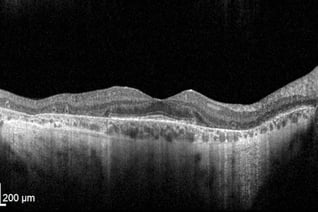

As with all retinal and optic nerve conditions, optical coherence tomography (OCT) has become fundamental for RP diagnosis and management. The earliest histopathological changes observable with OCT are shortening of the photoreceptor outer segments and general disorganization of the outer retina.

Progression of RP is visualized as continued thinning of the photoreceptor outer segments in addition to diminishing outer nuclear layer thickness. Atrophy of the photoreceptor layer and outer nuclear layer (which contains photoreceptor nuclei) is expected as RP targets rod then cone photoreceptors.

In advanced stages of RP, the photoreceptor outer segments and the outer nuclear layer may wither away completely. While the outer retina exhibits severe disorganization, the inner retina typically remains remarkably intact and may even thicken to some degree.

The bone-spicule pigmentation, from migrating RPE cells, may be demonstrated as hyper-reflected areas in the inner nuclear layer, outer nuclear layer, or subretinal space. The degree of hyper-reflected areas in the outer nuclear layer is associated with visual acuity. Thinning of the photoreceptor outer segments in the macular area is correlated with a decrease in visual field sensitivity. OCT is therefore useful in diagnosing, monitoring, and visualizing structural changes in RP patients.

Furthermore, OCT is valuable in diagnosing other RP-associated macular conditions such as cystoid macular edema (CME), epiretinal membranes (ERM), and macular holes. CME is one of the more common RP-associated retinal findings and can be visualized with OCT as cystic-like fluid spaces in the inner nuclear layer, outer nuclear layer, outer plexiform layer, and ganglion cell layer of the retina.